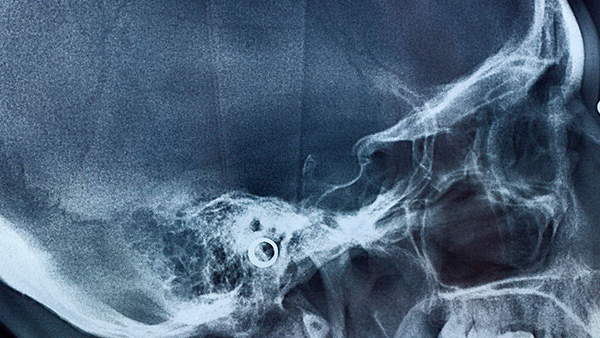

Condition / Treatment Brain and Spine Trauma